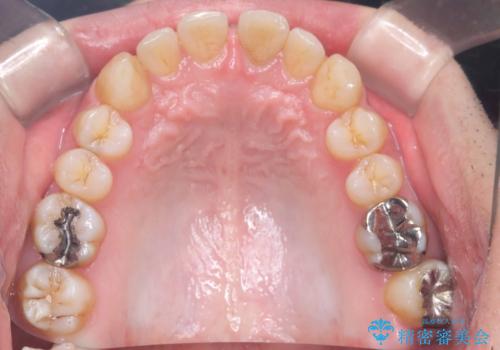

- 前歯の隙間と歯のデコボコを主訴にご来院された患者様です。

加えて、上下の奥歯が全く咬み合わないシザーズバイトの状態も認められました。

矯正検査の結果、非抜歯でインビザラインによる治療が可能と判断し、治療を行いました。

歯の隙間とデコボコ、シザーズバイトも改善され、咬み合わせや見た目が整い、患者様にも大変ご満足いただけました。